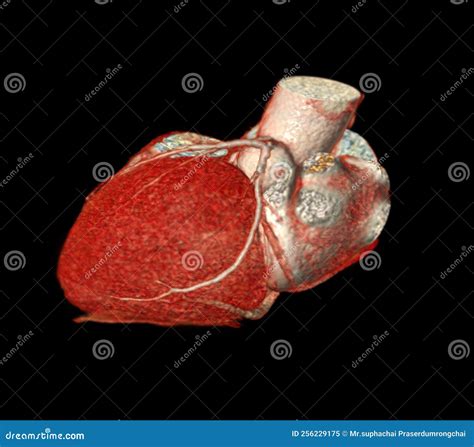

When it comes to diagnosing heart conditions, precision is paramount. A Cardiac CT, also known as a coronary computed tomography angiography (CCTA), has revolutionized the way medical professionals visualize the complex structures of the heart. By utilizing advanced X-ray technology coupled with powerful computers, this non-invasive diagnostic tool creates detailed, three-dimensional images of your heart, its arteries, and the surrounding tissues. Whether you are experiencing unexplained chest pain or have known risk factors for cardiovascular disease, understanding how this procedure works can help alleviate anxiety and prepare you for your medical journey.

At its core, a Cardiac CT scan is an imaging test that allows cardiologists and radiologists to see if your coronary arteries are narrowed or blocked by plaque buildup—a condition known as atherosclerosis. Unlike traditional stress tests, which provide functional information about how your heart handles exertion, a cardiac CT provides anatomical information. It captures images of the heart while it is beating, using sophisticated gating technology to synchronize the image acquisition with your heart rhythm.